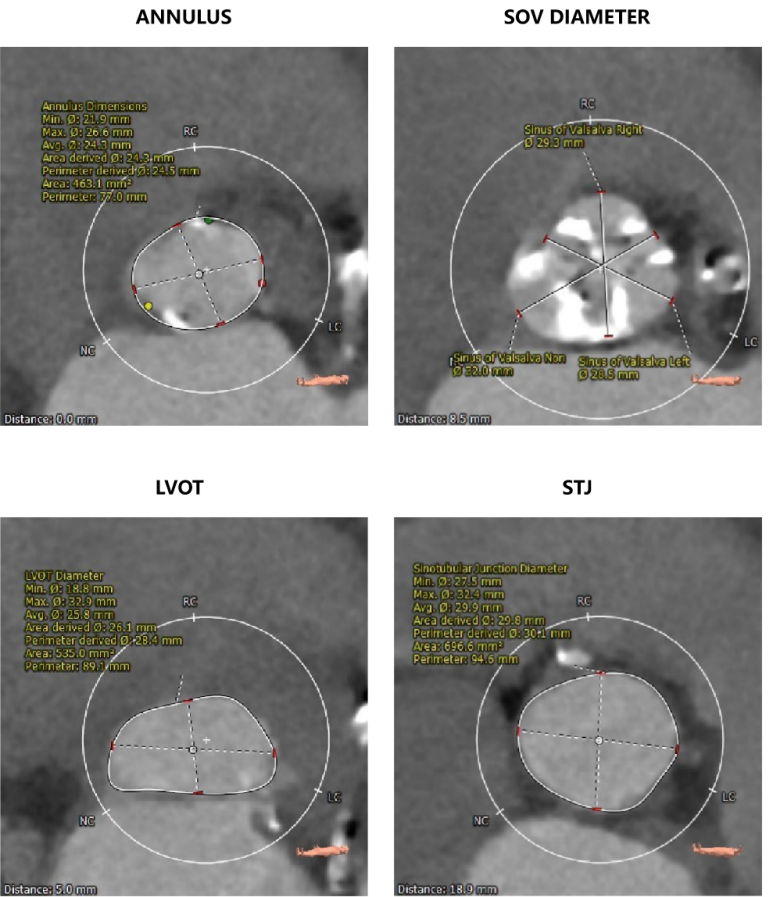

CT数据显示该患者为三叶三窦式主动脉瓣。

主动脉瓣瓣环周长77.0mm,平均周长径 24.5mm;LVOT周长89.1mm,平均周长径28.4mm;SOV:28.5mm*29.3mm*32.0mm;STJ平面周长94.6mm;瓣叶增厚,瓣上钙化明显,HU850积分1341mm³, HU560积分2499mm³,升主动脉最大直径44.1mm。